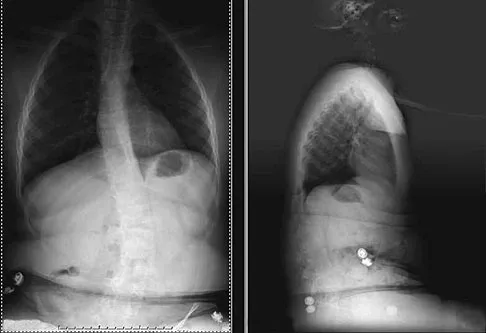

A 24-year-old woman has a spleen laceration and hypotension. Radiographs reveal a pulmonary contusion and a displaced mid-diaphyseal fracture of the femur. The trauma surgeon clears her for stabilization of the femoral fracture. What technique will offer the least potential for initial complications?

Explanation

Question 66High Yield

Figures 36a and 36b show the radiographs of a 48-year-old woman who smokes cigarettes and sustained a segmental femoral shaft fracture in a motor vehicle accident 9 months ago. Initial management consisted of stabilization with a reamed statically locked intramedullary nail. She now reports lower leg pain that increases with activity. In addition to advising the patient to quit smoking, management should include

Explanation

Question 93 High Yield

A 25-year-old man is brought to the emergency department following a motor vehicle accident. Extrication time was 2 hours, and in the field he had a systolic blood pressure by palpation of 90 mm Hg. Intravenous therapy was started, and on arrival in the emergency department he has a systolic blood pressure of 90 mm Hg with a pulse rate of 130. Examination reveals a flail chest and a femoral diaphyseal fracture. Ultrasound of the abdomen is positive. The trauma surgeons take him to the operating room for an exploratory laparotomy. At the conclusion of the procedure, he has a systolic pressure of 100 mm Hg with a pulse rate of 110. Oxygen saturation is 90% on 100% oxygen, and he has a temperature of 95.0 degrees F (35 degrees C). What is the recommended treatment of the femoral fracture at this time?

Detailed Explanation

Question 95 High Yield

What type of injury is considered the major mechanism of cervical fracture, dislocation, and quadriplegia in contact sports and diving?

Detailed Explanation